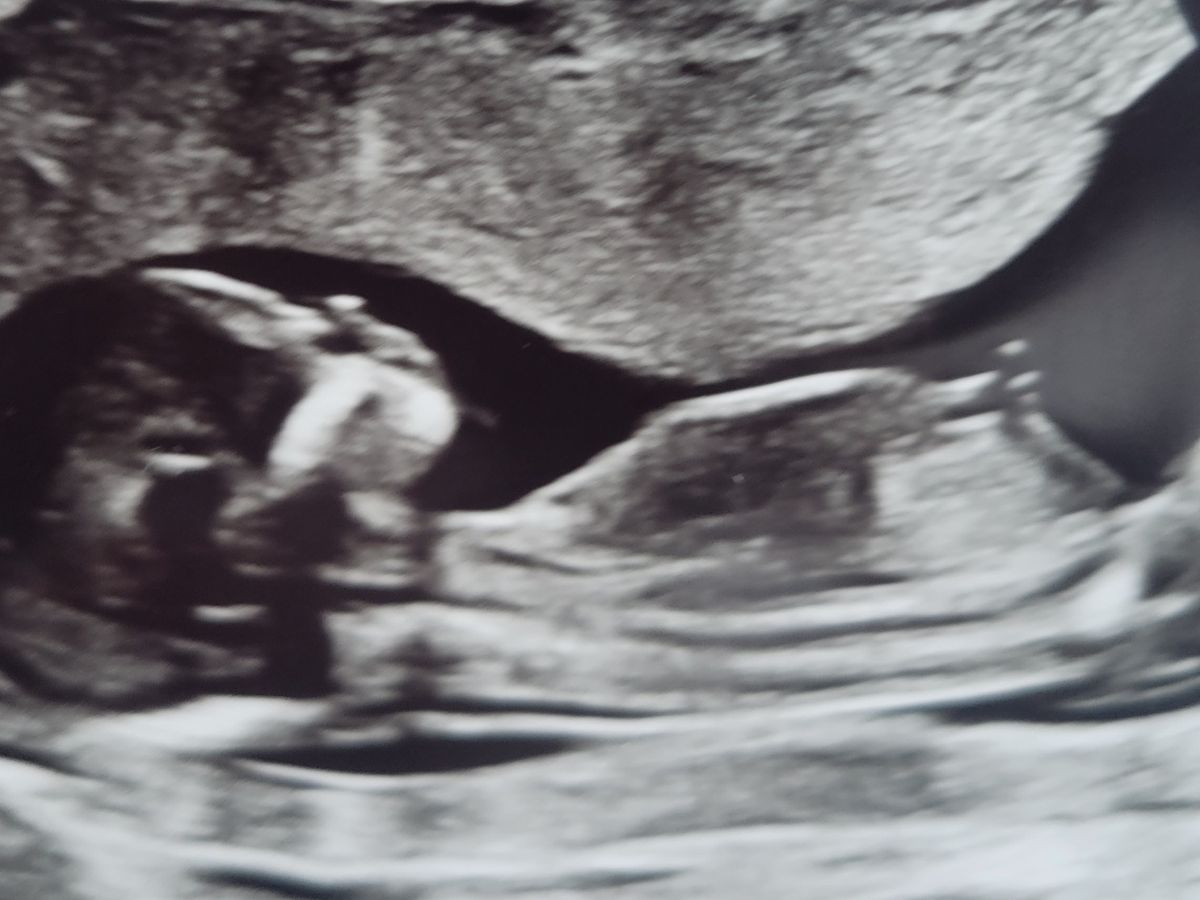

After 12 years of trying, infertility treatments, a failed IVF cycle and a miscarriage last year, we were thrilled to find out we were expecting again on December 15, 2022! Baby Girl Forte is due August 2023.

To explain it as easily as possible, I had a blood transfusion last year, due to my miscarriage, that created antibodies to foreign antigens and the baby has just tested positive for those antigens which means she is 100% at risk for fetal anemia and hydrops. A rare and potentially fatal disorder. We were referred to a top maternal fetal medicine doctor(the closest option) in LA at the UCLA Medical Center. After meeting with specialist she has deemed that it is necessary for weekly trips to monitor the baby, and possibly biweekly near the end. The only treatment option is weekly monitoring with MCA doppler scans and blood transfusions in utero if needed(hopefully not).